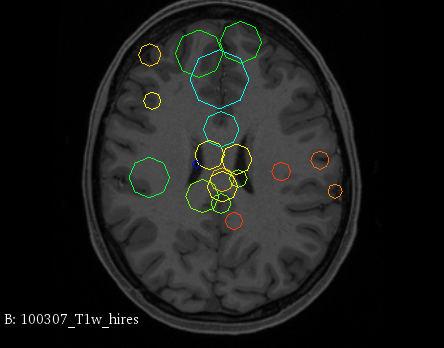

Figure 3 provides a scale-space visualization of feature matches for a single pair of MZ twins and NT siblings, where scale information is represented using the circle radius. Note that circles represent the intersection of 3D spheres with the visible slice and, thus, non-intersecting features are hidden in this 2D visualization.

It can be seen that different image modalities generally result in distinct, complementary feature correspondences throughout the brain, allowing a rich characterization of both anatomical and connectivity structure. In T1 and T2 images, features are mainly located in the frontal lobe, corpus callosum and brain stem. Smaller-scale features are also visible along various cortical regions, as well as in sub-cortical structures near the basal ganglia. Although highly correlated, T1 images show significantly more feature matches than T2 images. Moreover, images based on diffusion measures have less matches than in structural modalities. These matches are located mostly inside or near to white matter: larger-scale features in the corpus-callosum, and smaller-scale ones in the brain stem and along white matter bundles. While not shown in the figure, the set of matches found by combining two modalities (e.g., T1 + T2) generally corresponds to the union of those obtained with these individual modalities.

Comparing different sibling types, we observe a greater number of matches between MZ twins than NT siblings. This observation, which is easier to visualize in T2 and GFA images, is consistent with other analyses on twin datasets. In terms of feature location and scale, no obvious pattern can be seen when comparing these two sibling types. However, a more detailed analysis would be required to validate this assertion.